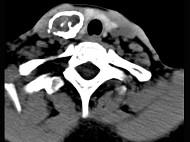

问题 50岁女性患者,体检发现右侧甲状腺有较硬结节,CT扫描如图所示,请选择正确的描述和答案()

选项 A.右侧甲状腺内见稍低密度影,周边围以环形致密钙化影 B.肿块影与周围结构分界清楚 C.考虑为结节性甲状腺肿 D.考虑为甲状腺癌 E.考虑为甲状腺腺瘤钙化

答案 ABE